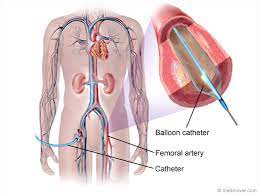

Value added benefits of the Angiography:

Ø Doctor consultation charges

Ø Lab tests and diagnostic charges

Ø Room charges inside hospital during the procedure

Ø Surgeon Fee

Ø Nursing charges

Ø Hospital surgery suite charges

Ø Anesthesia charges

Ø Routine medicines and routine consumables (bandages, dressings etc.)

Ø Food and Beverages inside hospital stay for patient and one attendant.

Extra benefits:

ü Interpreter

ü Visa assistance

Ø Site tourism of the city

Ø Follow up with the doctor

Ø Airport pick up and drop

Ø Free online consultation with the doctor

Ø Priority appointments with the doctor

Ø Room upgrade from sharing to private